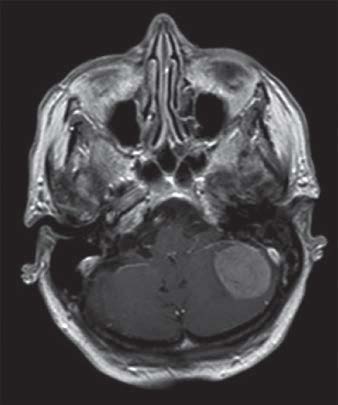

IRM d’une femme de 88 ans atteinte d’un méningiome de la fosse cérébrale postérieure